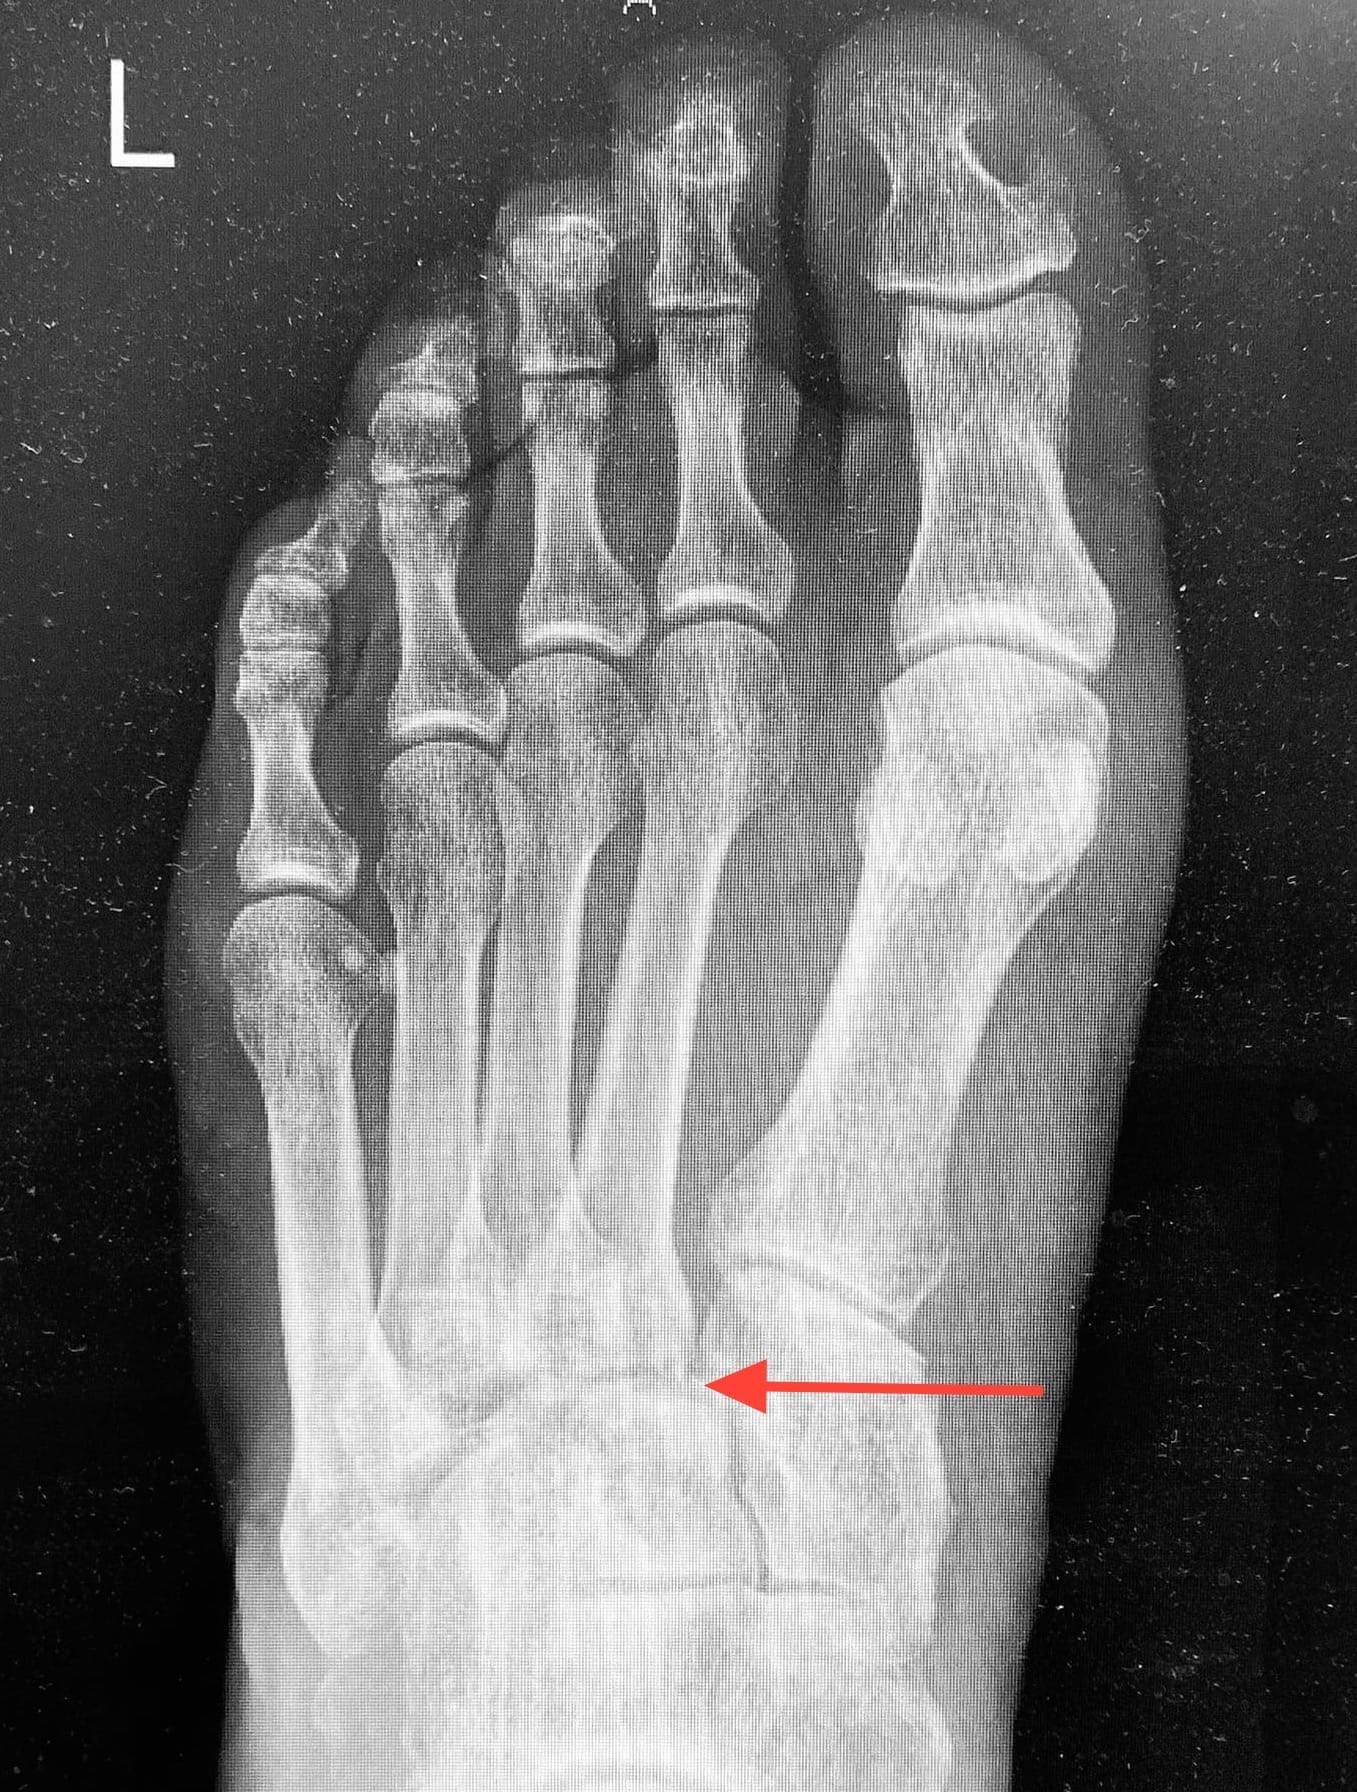

A 66-year-old man presented with persistent swelling and pain in his left foot after a trip and fall at a bus stop. At his first clinic visit he was able to partially weight-bear. Examination documented tenderness over the midfoot and base of the first metatarsal, but no plantar bruising was recorded. An X-ray was initially interpreted as normal and formally reported as showing no fracture or dislocation, so the injury was treated as a sprain.

A repeat X-ray confirmed the diagnosis. There was gross subluxation of the first and second tarsometatarsal joints with 6–7 mm displacement, and a possible cuboid fracture. The patient was urgently referred to orthopaedics for open reduction and internal fixation.

The initial x-ray was reported normal by a consultant radiologist. The size of the first inter- metatarsal space was suspicious and on closer review there was a subtle abnormality; a small step at the junction of the base of the second metatarsal with the middle cuneiform(see arrow).